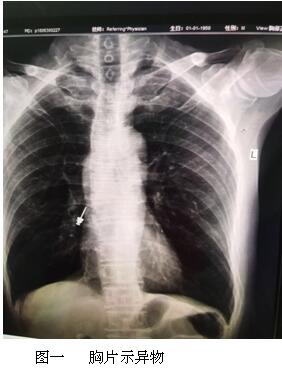

六月最后一天的上午,內(nèi)鏡中心來(lái)了一名特殊的患者,患者表情焦慮,訴于外院補(bǔ)牙時(shí),不小心把補(bǔ)牙的一顆螺絲吞下,現(xiàn)咽喉部明顯不適,于我院耳鼻喉行喉鏡檢查,未見(jiàn)明顯異物,內(nèi)鏡中心伍友興主任聽聞后,考慮異物可能卡在食管上段,持鏡給予患者行胃鏡檢查,但是反復(fù)觀察食道、胃及十二指腸,并未找到患者所描述的異物。是不是有可能異物已經(jīng)掉入十二指腸以下的消化道了呢?如果已經(jīng)掉入小腸,這一顆大約長(zhǎng)2cm的螺絲,表面無(wú)明顯銳利邊緣,刺破腸管的可能性較小,可自行隨大便排出,正當(dāng)我們準(zhǔn)備松一口氣告訴患者胃鏡下未見(jiàn)明顯異物時(shí),患者輕輕的咳嗽兩聲引起了伍主任的注意,“快去行胸部照片,異物可能掉入氣管”伍主任說(shuō)到,患者遂行胸部照片,見(jiàn)異物果然出現(xiàn)在患者右側(cè)的肺里,為進(jìn)一步確定異物部位,給予行胸部CT檢查,并積極聯(lián)系呼吸內(nèi)科豐偉民主任,黃雪英老師與豐主任兩人密切配合,在支氣管鏡下看到右側(cè)支氣管下段,找到了讓人揪心的異物,順利取出,此刻患者緊縮的眉頭終于舒展開來(lái),連連向我們醫(yī)務(wù)人員道謝。